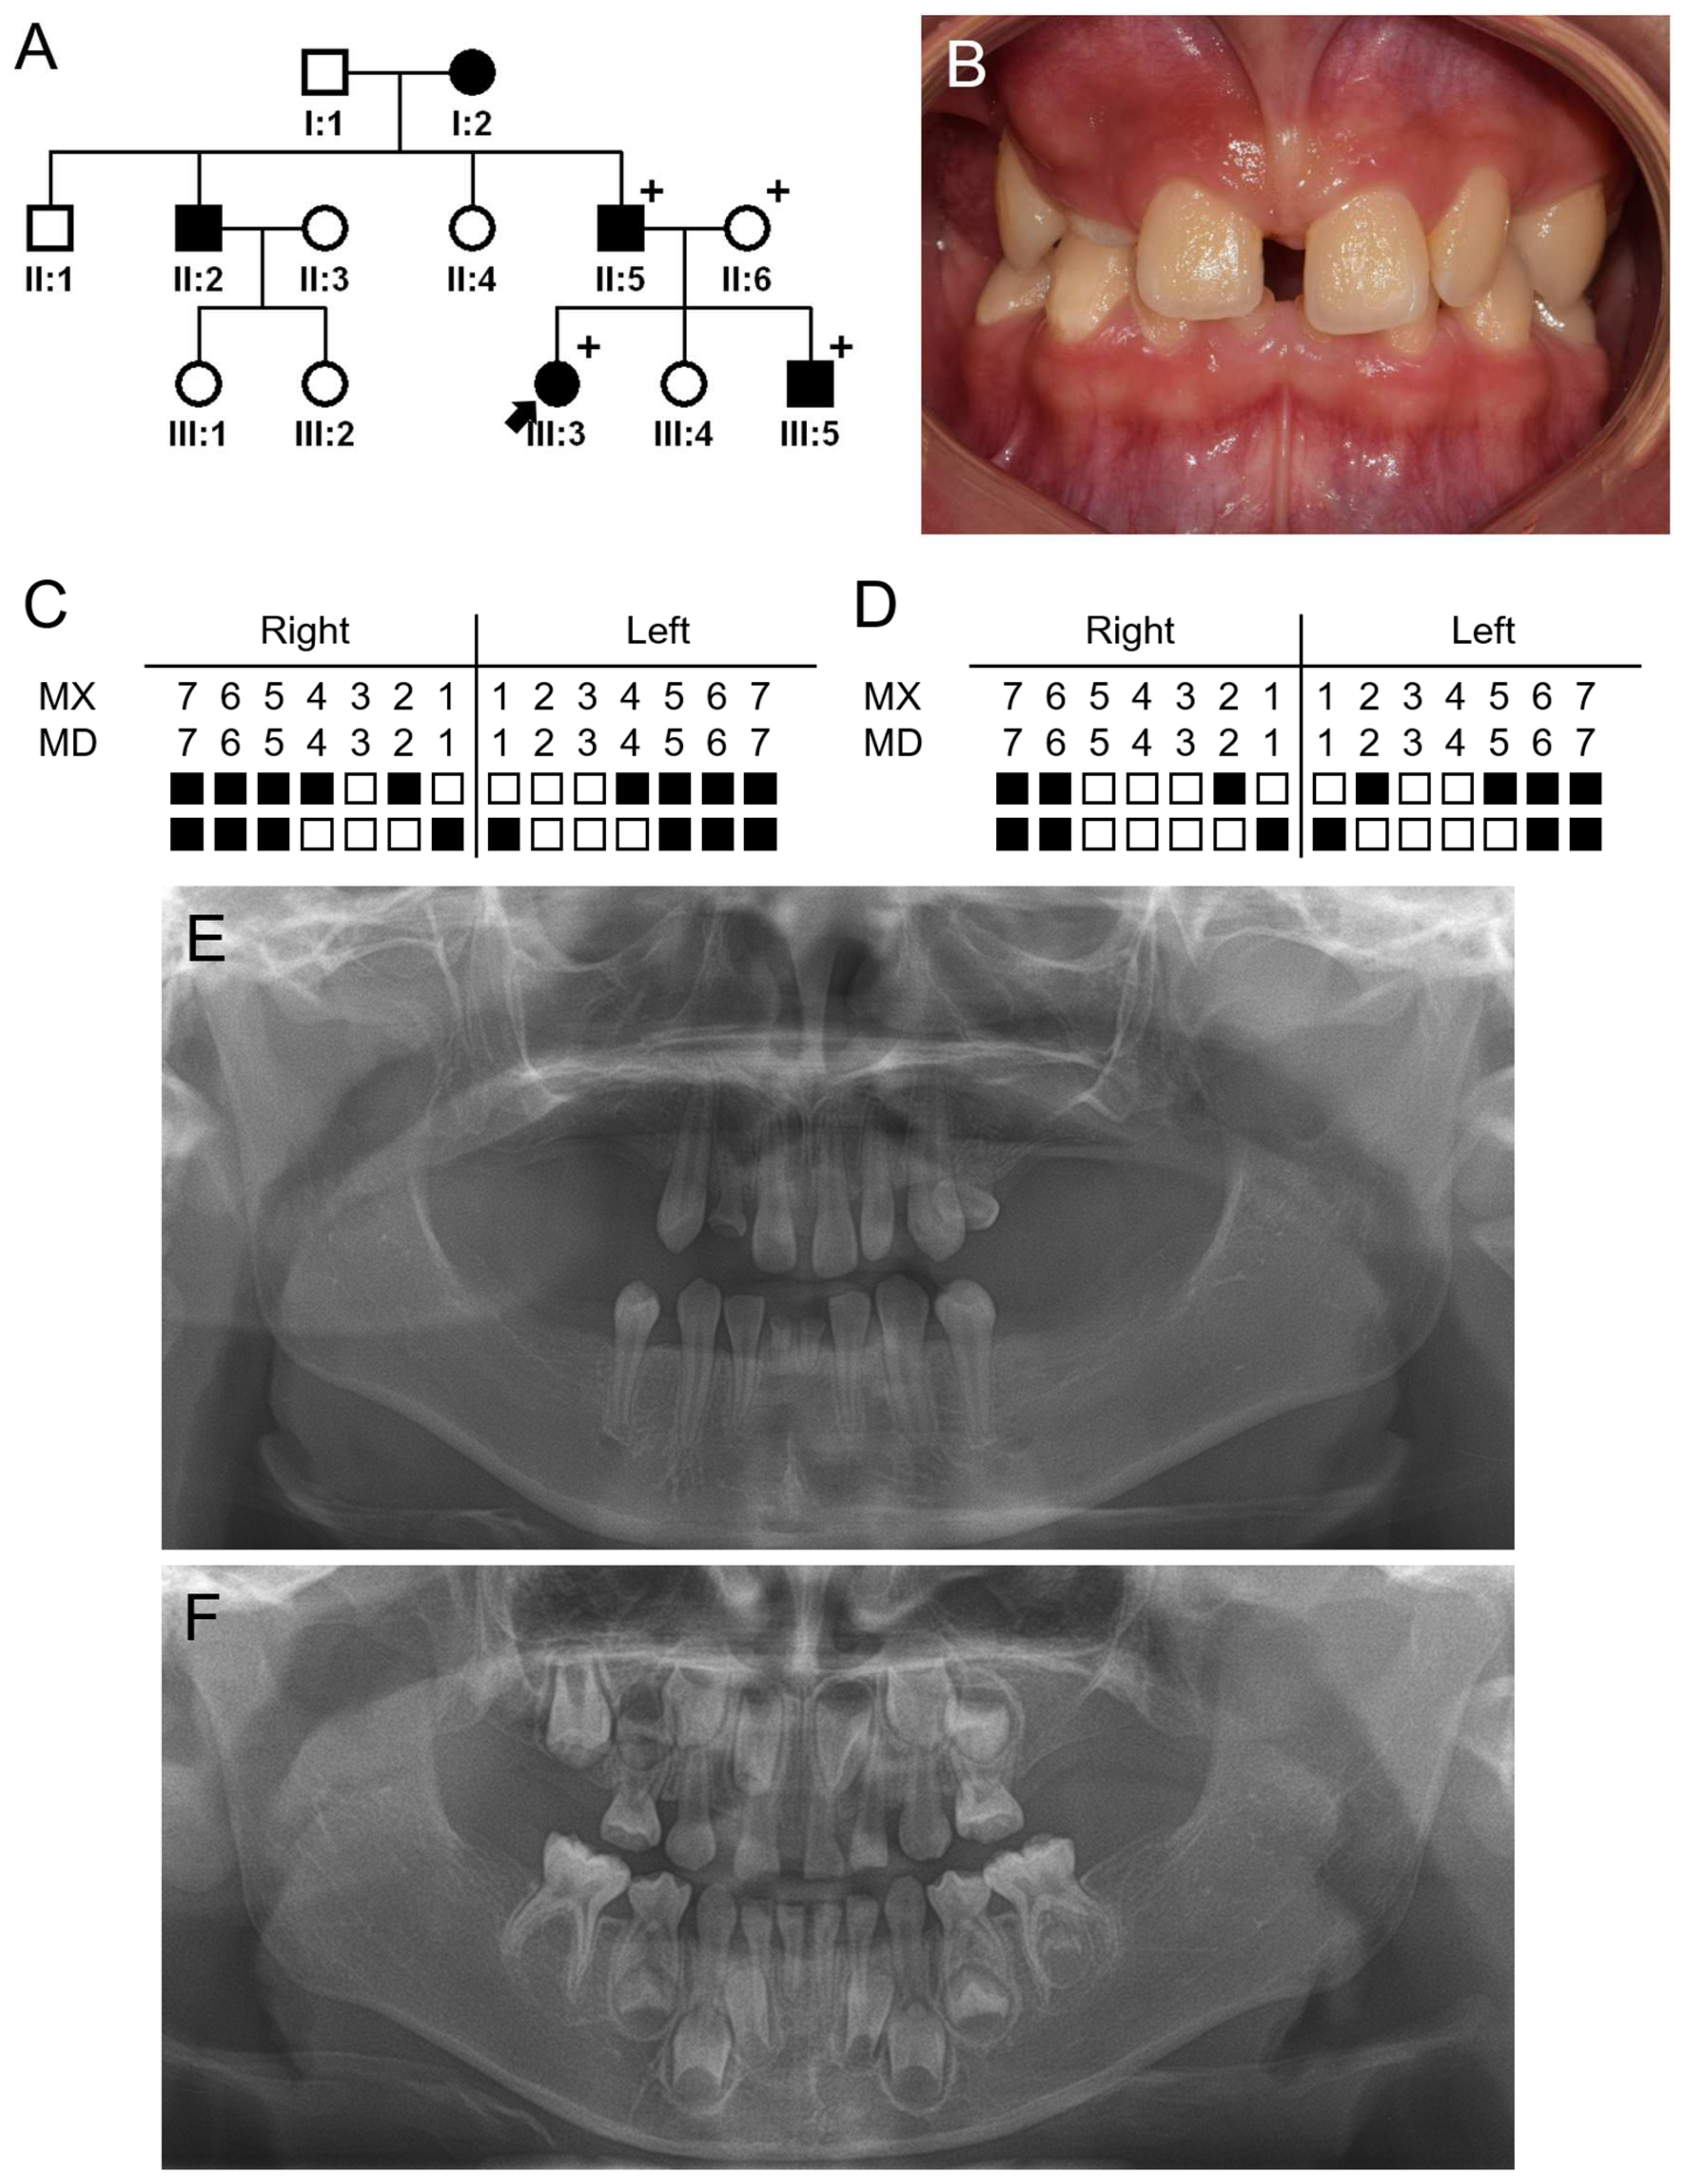

3.1. Family 1